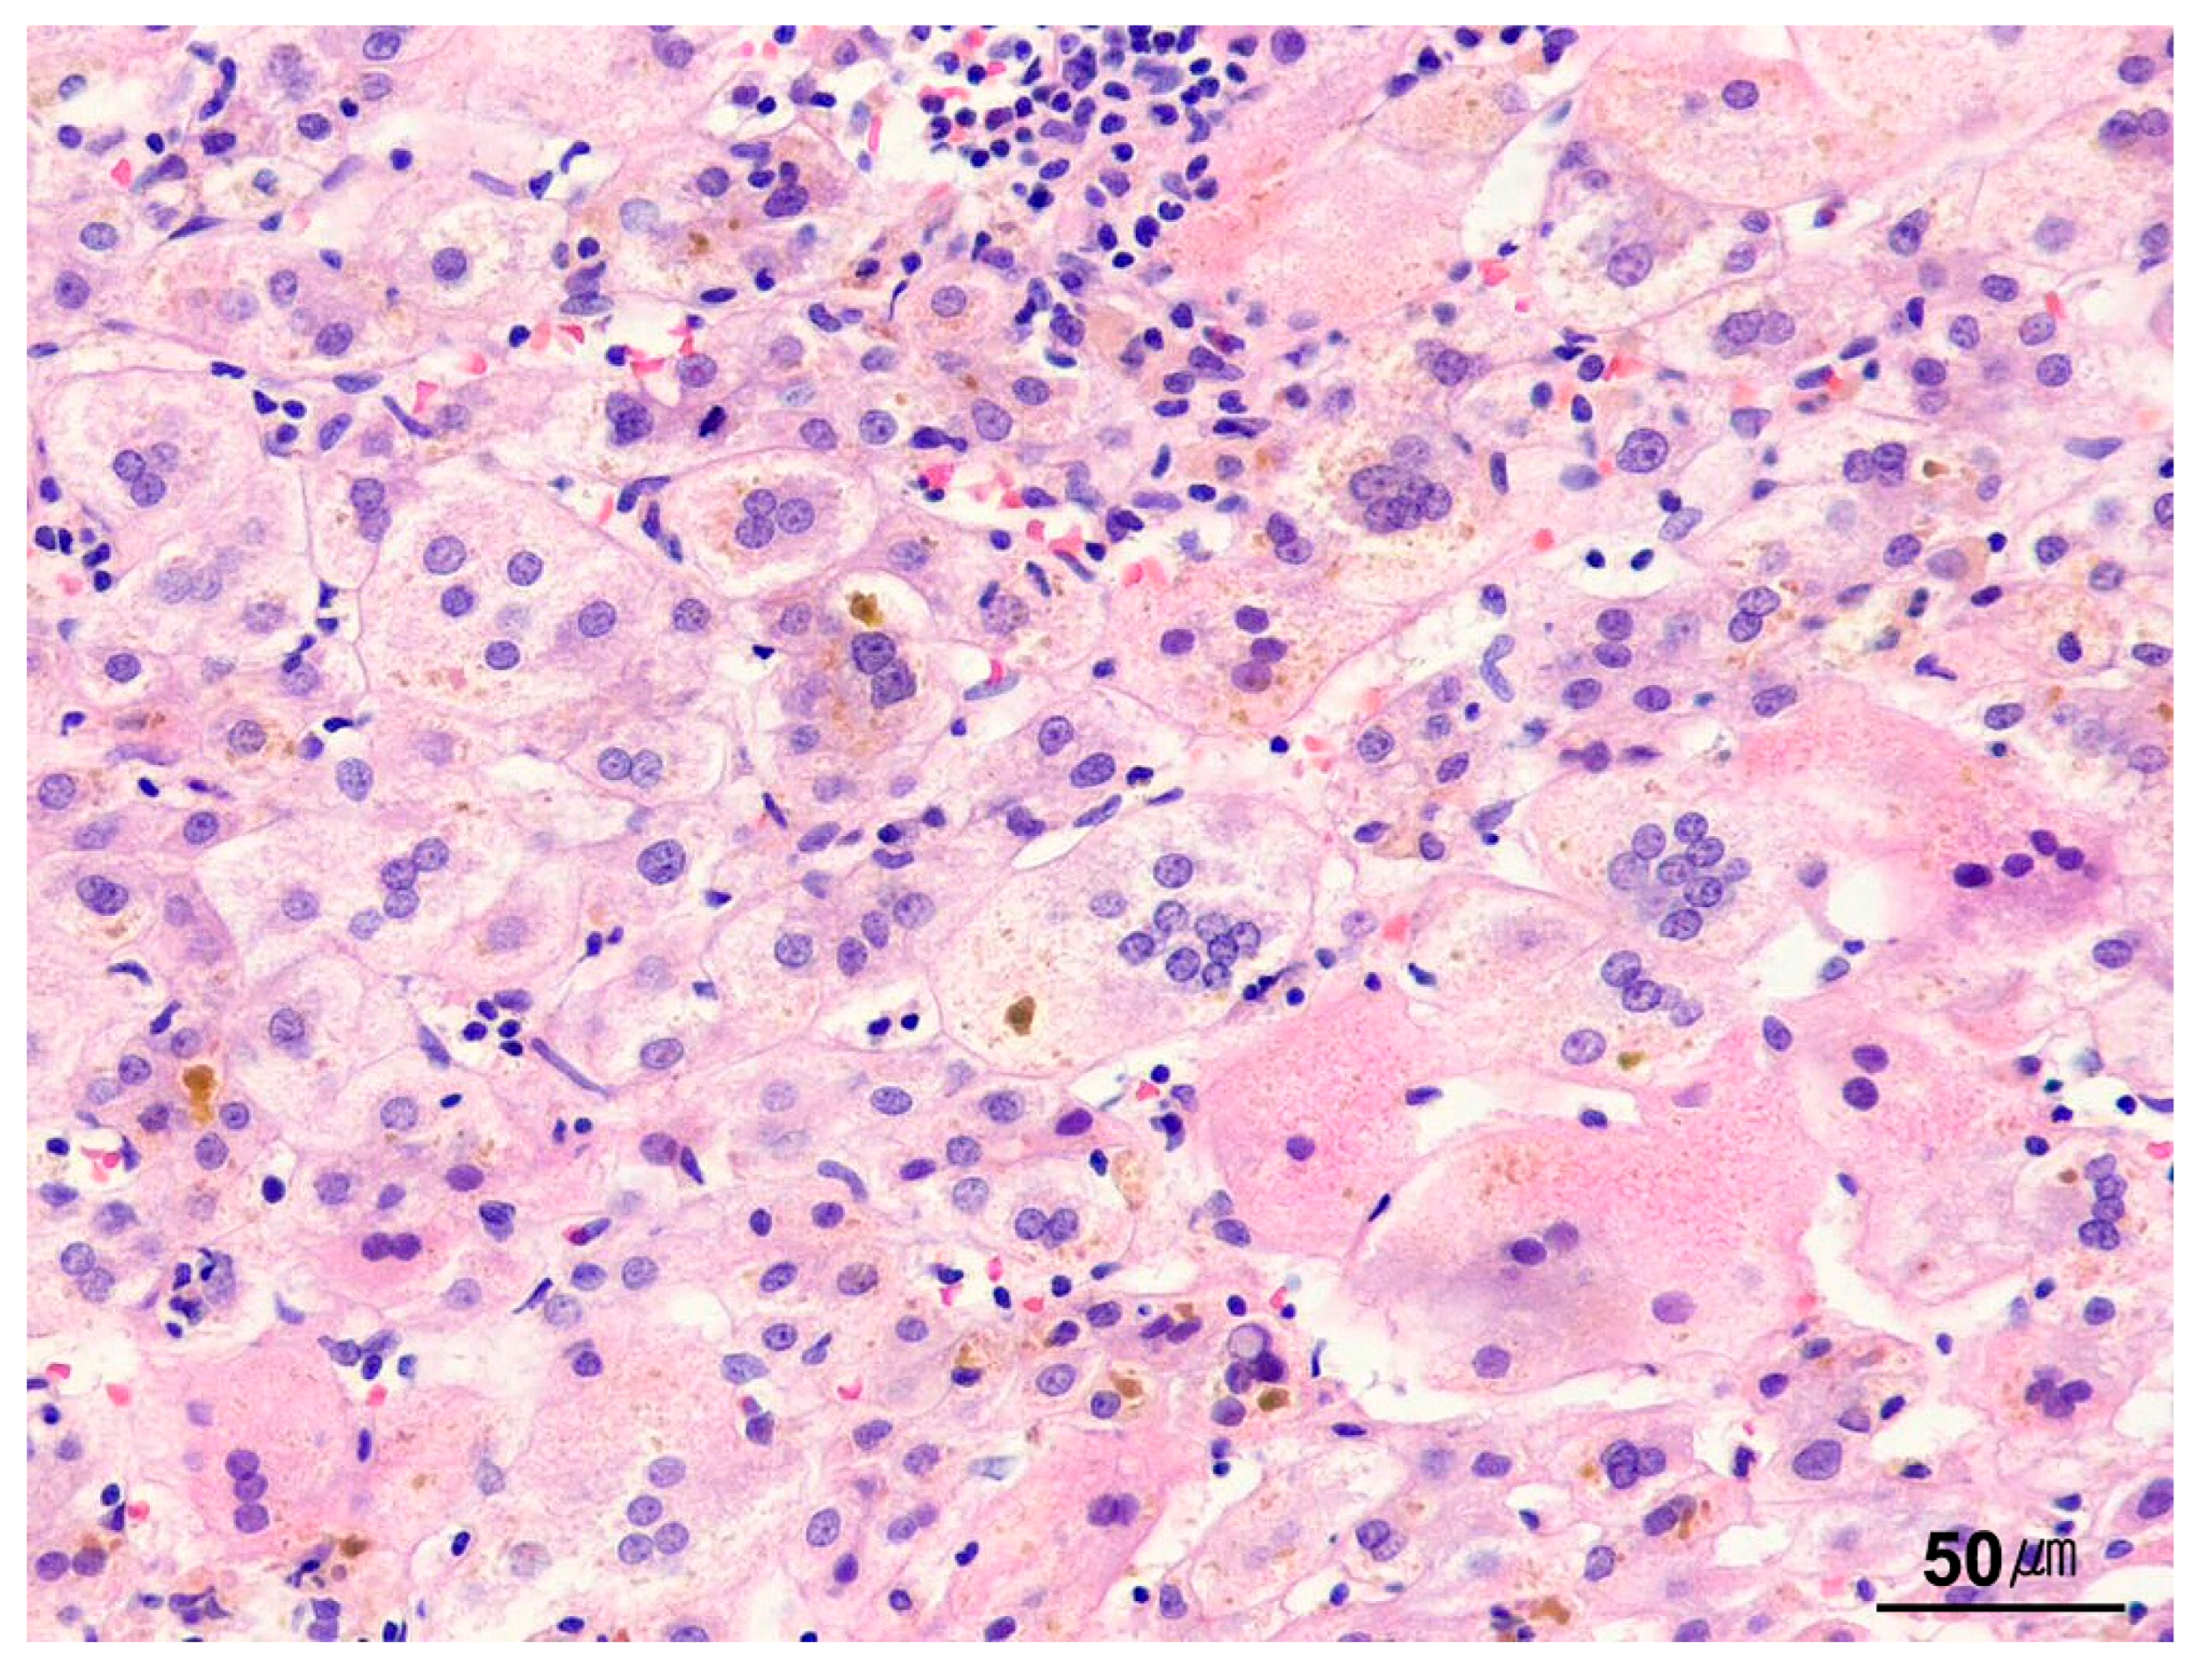

9.4.3. Giant-Cell Transformation

9.4.4. Hepatocyte Inclusions